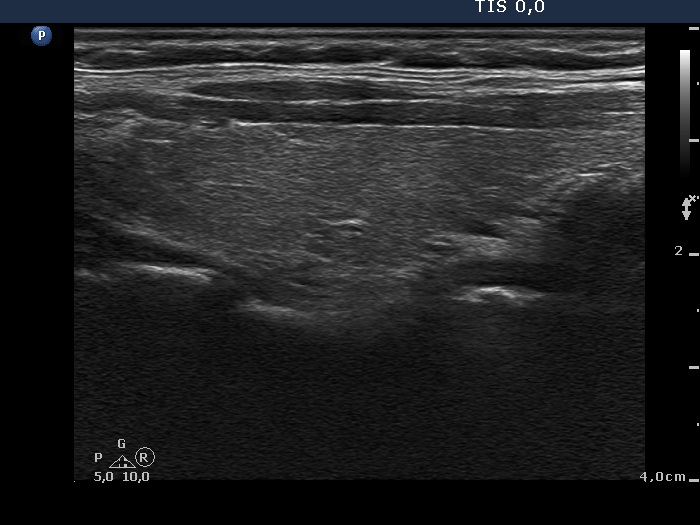

Lymph nodes in the neck - Case 1205 (ultrasonographic picture 2)

Right lobe, longitudinal scan.